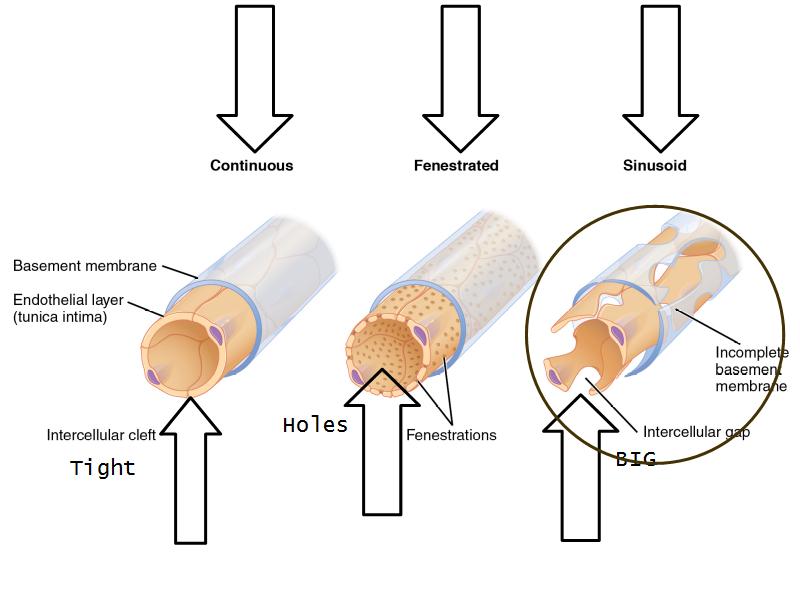

How does the pituitary and hypothalamus communicate?2 ways